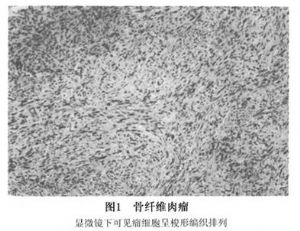

組織學檢查可將纖維肉瘤分爲:分化好的、分化中等、分化差的腫瘤,或是將其分爲Ⅰ~Ⅳ級,級數越高代表分化越差。腫瘤分級、分類的標準是客觀的,是由細胞數、有絲分裂活動、膠原的產生、核的形態及全部組織類型進行綜合評價。大多數纖維肉瘤屬中等,或是分化差的類別,惡性程度高的病人生存率低。

分化好的纖維肉瘤是由長方形和梭形細胞所組成,細胞核細長肥碩,染色較淡,細胞形態和大小尚一致,呈束狀排列,有時呈漩渦狀,細胞分佈較疏鬆,胞質豐富,間質中有較多的膠原纖維,核分裂僅偶爾見到。分化較差的骨纖維肉瘤中,細胞數目增加,細胞排列緊密,相應的膠原含量減少;核較大呈圓形或卵圓形以及不規則的,染色質粗大,成叢且分佈不規則,常見有核仁較明顯,核分裂活動增加(圖1,2)。在分化差的纖維肉瘤中常有壞死及出血。